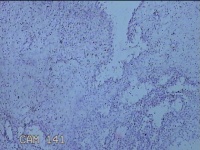

性别

女

年龄

25岁

临床诊断

1.宫角妊娠 2.宫腔粘连 3.先兆流产

一般病史

停经36天,阴道流血半天。

标本名称

宫腔内组织

大体所见

灰白暗红色不规则碎组织3x2.8x0.7cm一堆,未发现明显的绒毛样组织。